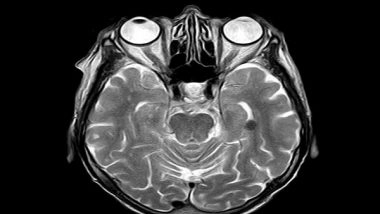

The new pathway, originating in a bundle of brain stem nerve fibres called the median raphe nucleus, acts in opposition to a previously identified reward/aversion pathway that originates in the nearby dorsal raphe nucleus.

To further study the reward and aversion nerve pathways of the brain, Hokkaido University neuropharmacologist Yu Ohmura and Kyoto University pharmacologist Kazuki Nagayasu, together with colleagues at several universities in Japan, focused their attention on the median raphe nucleus. This region has not received as much research attention as its brain stem neighbour, the dorsal raphe nucleus, even though it also is a source of serotonergic nerve fibres.